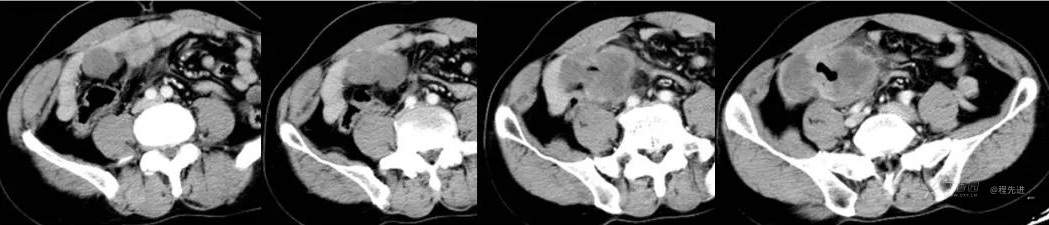

CT平扫